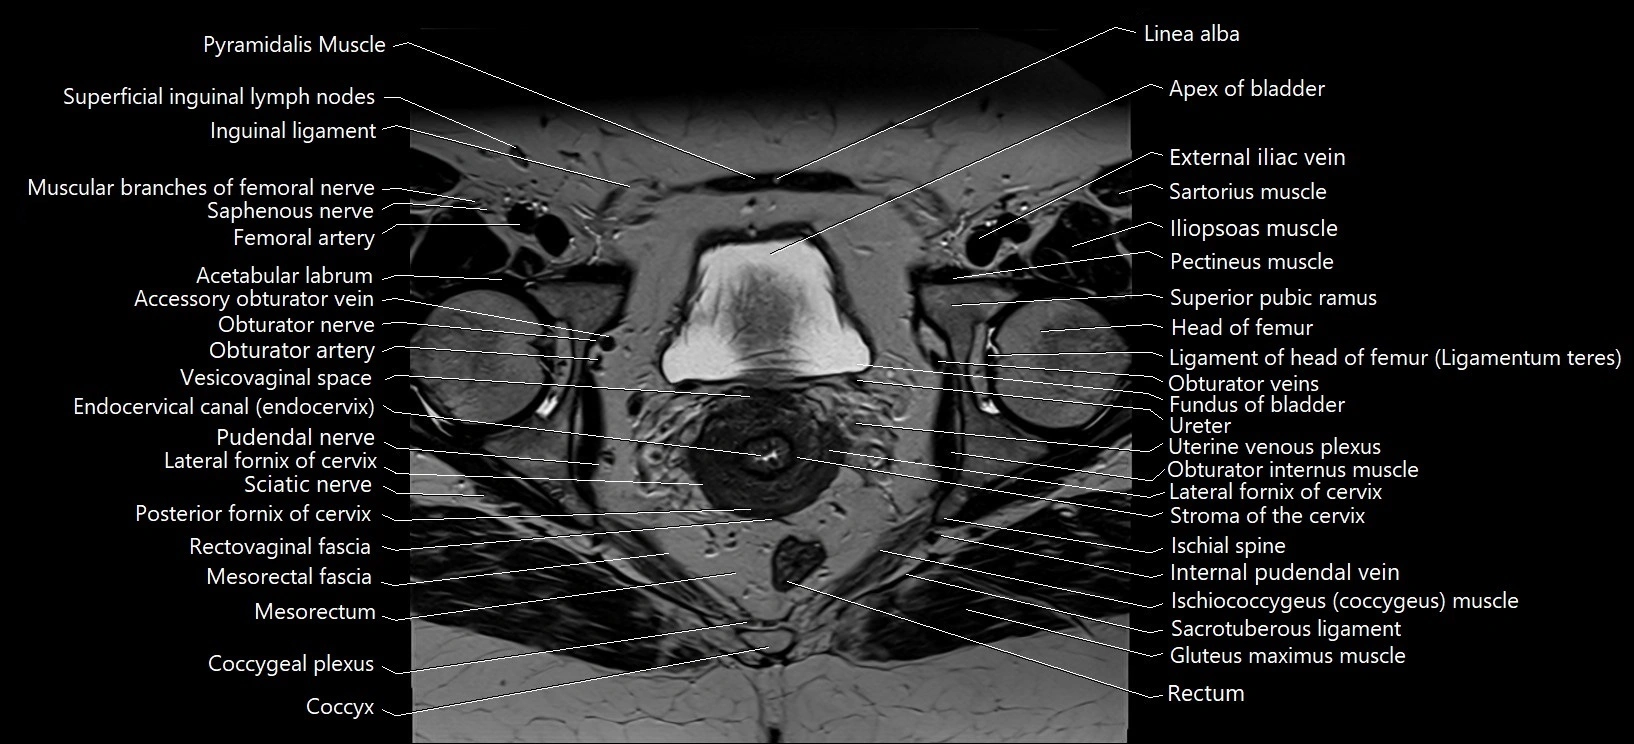

- Acetabular labrum

- Apex of urinary bladder

- Body of urinary bladder

- Cervix of uterus

- Coccygeal plexus

- Coccyx

- Common iliac vein

- Endocervical canal

- External iliac vein

- Fundus of urinary bladder

- Head of femur

- Iliopsoas muscle

- Iliopsoas tendon

- Inguinal ligament

- Inguinal lymph nodes

- Internal pudendal vein

- Ischial spine

- Lateral fornix of cervix

- Mesorectal fascia

- Mesorectum

- Obturator internus muscle

- Obturator nerve

- Obturator veins

- Pectineus muscle

- Piriformis muscle

- Posterior fornix of cervix

- Pubic symphysis

- Pudendal nerve

- Pyramidal muscle (pyramidalis muscle)

- Rectum

- Sacrotuberous ligament

- Sartorius muscle

- Sciatic nerve

- Stroma of the cervix

- Superficial inguinal lymph nodes

- Superior pubic ramus

- Ureters

- Uterine venous plexus

- Uterosacral ligament

- Vesicovaginal space